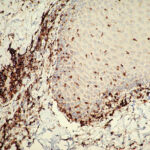

Mycosis Fongoïde =التفطر الكمئي